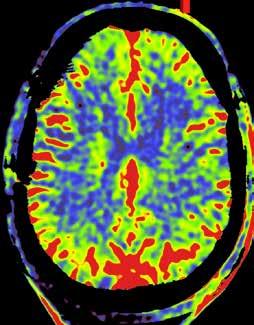

Om het probleemgebied duidelijk in kaart te brengen, werd uitgewe ken naar een perfusiescan die via contrastvloeistof de doorbloeding van de hersenen in beeld brengt. Menovsky: ‘We interpreteren de beelden altijd samen met de radioloog. Vanuit hun vakgebied zien ze dingen die wij niet zien, en omgekeerd.’ Op de beelden was te zien dat een bepaald deel van

Op het linkerbeeld is te zien dat de bloedvaten in de hersenen meer moeite hebben om de bloedtoevoer in de hersenen te garanderen. Op het beeld rechts, na de operatie, is het probleem hersteld.

de hersenen onvoldoende door bloed was. ‘Op basis daarvan was een bypass de beste behandeling. Tijdens een operatie maakten we een luik in de schedel en verbonden we een slagader van de huid met het deel van de hersenen dat onvol doende doorbloed was. Dat heeft het probleem opgelost voor die patiënt. Met dank aan de precieze beelden. Zonder die beelden was de ingreep nooit mogelijk geweest.’